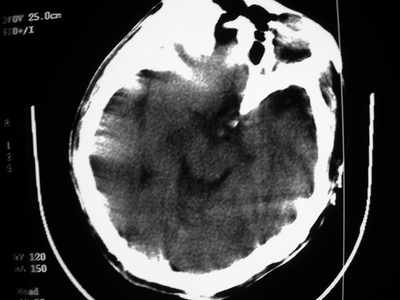

以下是引用卜一在2007-1-19 15:29:00的发言:[br]治疗前:1月14日右侧额叶皮质下低密度影,而治疗后:1月18日右侧阴影消失,新近出现左侧额叶侧脑室前角旁大片状低密度影,边缘模糊。支持—双侧额叶后部缺血性脑梗塞。